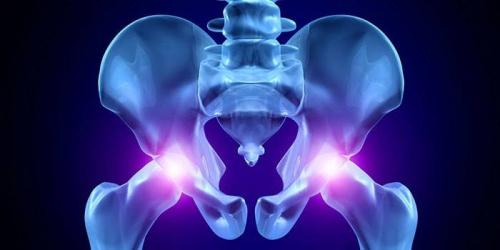

Тазобедренный сустав. Что такое тазобедренный сустав

Что соединяет нижние конечности и верхнюю часть тела, помогает удерживать вес, обеспечивать осанку? С этими задачами справляется самый крупный, мощный сустав в человеческом организме. Ему приходится испытывать огромные нагрузки в течение длительного времени. Тазобедренный сустав – это сочленение костей, которое благодаря работе мышц, сухожилий помогает совершать многообразные виды движений во всех плоскостях. Среди них:

Анатомия

Строение ТБС позволяет человеку передвигаться, проводить силовые упражнения, иметь надежную опору. Анатомия тазобедренного сустава гарантирует мобильность, за счет особенностей его структуры:

- тазобедренная кость оканчивается шарообразной головкой;

- ее фиксирует углубление, расположенное в тазу – вертлужная впадина;

- для смягчения движения она выстлана хрящевой тканью, имеет гелеобразную смазку;

- в полости околосуставной сумки находится синовиальная жидкость, уменьшающая трение, питающая хрящ.

Кроме этого, имеются не менее важные элементы:

- прочная суставная капсула, четыре мощные связки – обеспечивают поддержку, предупреждают вывих, состоят из соединительной ткани высокой плотности;

- мышцы, сухожилия, окружающие ТБС благодаря сокращениям организуют все движения;

- связка внутри соединяет край вертлужной впадины и тазобедренную головку имеет глубоко расположенные нервы и сосуды.